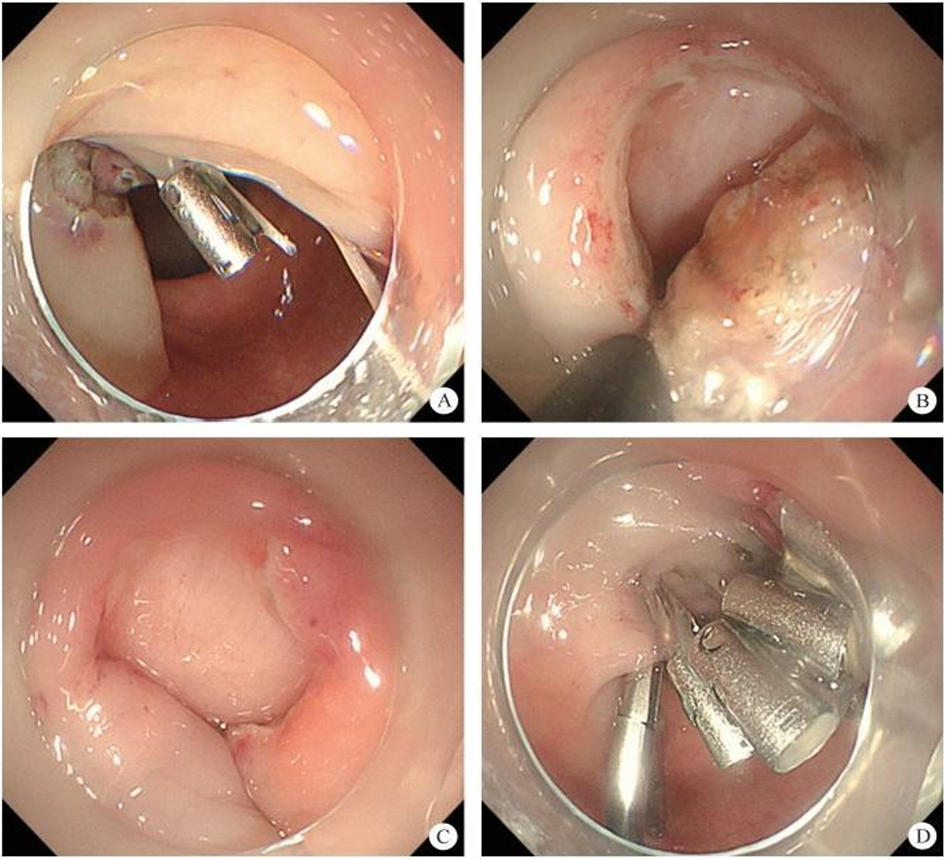

1. Peroral endoscopic myotomy (POEM). POEM has been widely used in the clinical treatment of achalasia; recently, applications in other parts of the human body have also been gradually emerging. In 2020, a study was conducted on a group of eight patients esophageal diverticulum and esophageal diverticulum treated by using POEM, also known as peroral diverticulum myotomy (D-POEM). D-POEM establishes a tunnel under the esophageal mucosa and incises the ridge between the diverticulum in the tunnel to make the diverticulum disappear. Postoperative follow-up of all patients, their preoperative symptoms were improved, and no adverse events were reported. Studies have shown that D-POEM has a certain effect on esophageal diverticulum, and that it is not affected by the position of the diverticulum and the length of the ridge between them, making it a safe and effective operation.